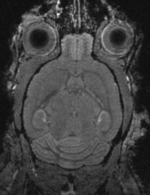

shown are, from left to right, panels of axial, sagittal and coronal views.

affine registered brains affine registered

registered brains after 5x5x5 nonrigid BSpline alignment registered brains after 5x5x5 nonrigid BSpline alignment